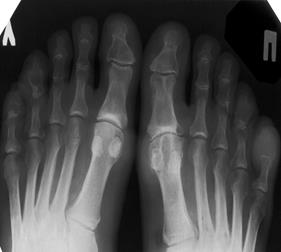

Больной К., 63 года, руководитель крупного предприятия, обратился к врачу с жалобами на нестерпимую боль, покраснение и припухание 1-м правом плюснефаланговом суставе, повышение температуры тела. Боли в суставе возникли внезапно ночью, среди полного благополучия. При опросе выяснилось, что деловые встречи с фуршетами часто перетекают в застолья (накануне присутствовал на корпоративной вечеринке). Самостоятельно принимал баралгин, но без эффекта. Объективно: больной повышенного питания (ИМТ 25). Признаки выраженного воспаления, болезненности и ограничение подвижности в 1-м правом плюснефаланговом суставе. На ушных раковинах - мелкие узелки, безболезненные, размером с просяное зерно. АД - 145/90 мм рт.ст. Пульс ритмичный, 96 ударов в мин. Живот мягкий, безболезненный. Печень, селезенка не увеличены.

На рентгенограмме правой стопы - субкортикальные кисты 1-го плюснефалангового сустава без эрозий. Мочевая кислота крови - 0, 44 ммоль/л. В синовиальной жидкости – L-10000-20000 кл/мм3. При поляризационной микроскопии синовиальной жидкости из сустава выявлены кристаллические ураты (3-30 мкм, иглообразной формы с двойным светопреломлением). Посев синовиальной жидкости отрицательный. OAK: Эр 4, 4 -1012/л, Нb - 125 г/л, L 16, 4-109/л, СОЭ - 25 мм/ч, Биохимия крови: ЛПНП– до 150 мг/дл, ЛНОНП – 50 мг/дл. холестерин – 8 ммоль/л. Общий анализ мочи: удельный вес -1020, лейкоциты 1-2 в поле зрения, белок-0, 033.